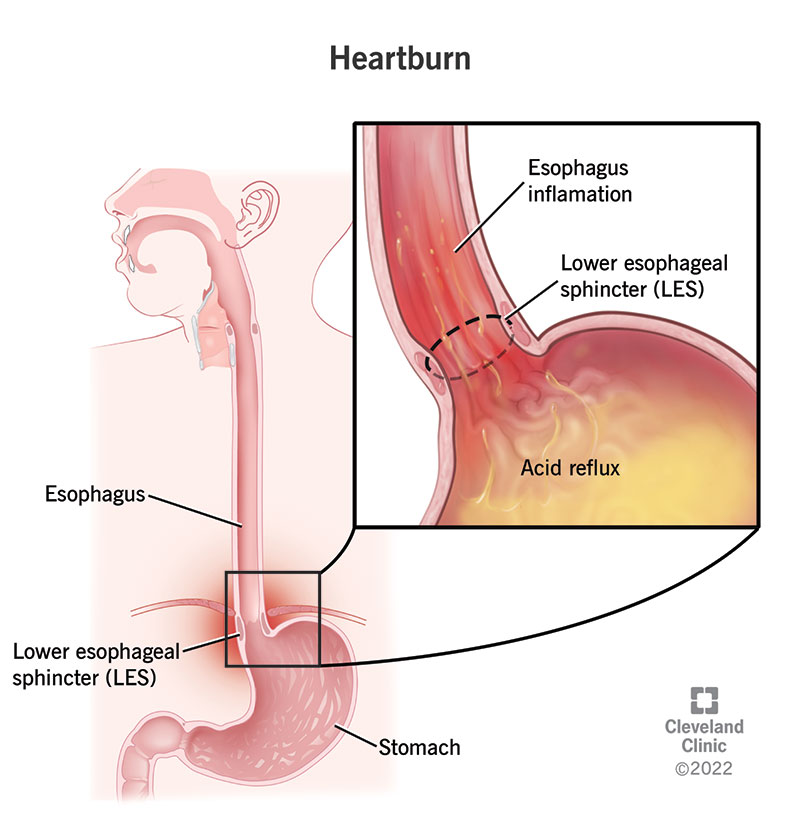

Heartburn: What It Feels Like, Causes & Treatment

Alkaline-Forming Foods Avoid Acid Eflux, Heartburn, GERD And Barrett’s …